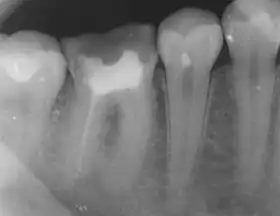

The body's response to microbial invasion